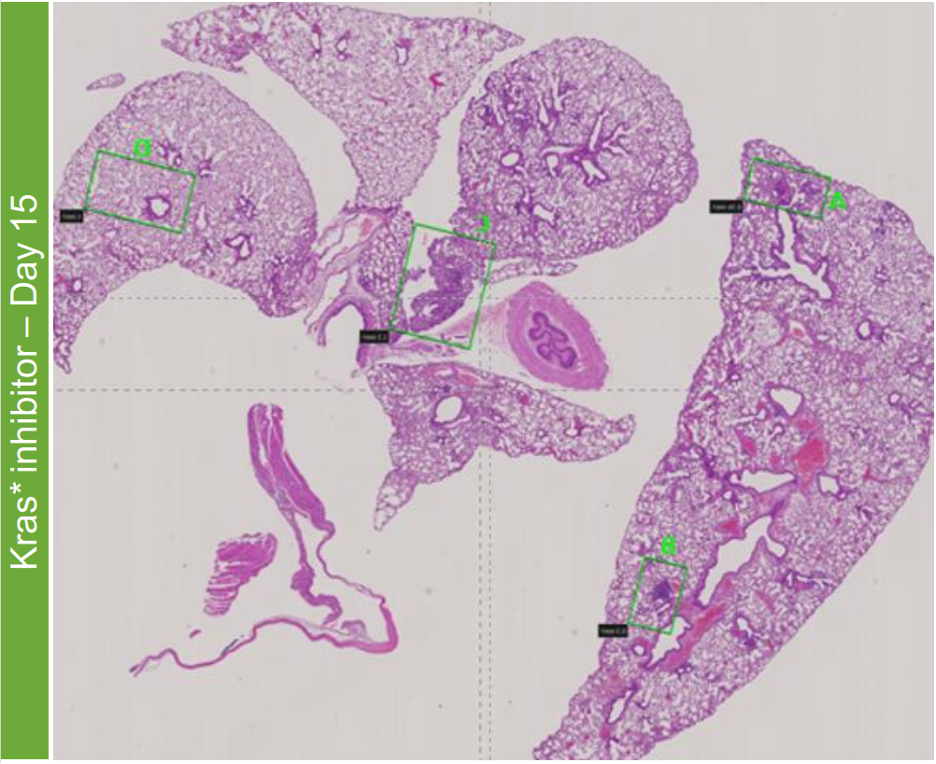

从AdFlp注入两个月后开始,小鼠每天注射Kras突变体的分子抑制剂。对照组小鼠(n=6)在第0天实施安乐,治疗组小鼠(n=5)在治疗9天或15天后实施安乐。使用2张4微米厚的连续组织切片分别进行H&E染色和CosMx检测。

在接受Kras抑制剂治疗之前,小鼠表现出LuAD和肺腺瘤。在使用Kras抑制剂进行药物治疗期间,病变的大小和组织学级别会逐渐降低。